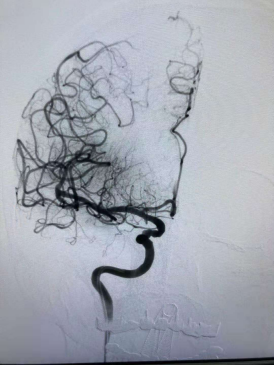

由于何奶奶有溶栓禁忌,不能行静脉溶栓治疗。医务人员当机立断,决定行全脑血管造影术+必要时机械动脉取栓术。造影发现何奶奶全身血管重度迂曲,右侧颈内动脉末端完全闭塞。

取栓前脑血管造影显示右侧颈内动脉闭塞